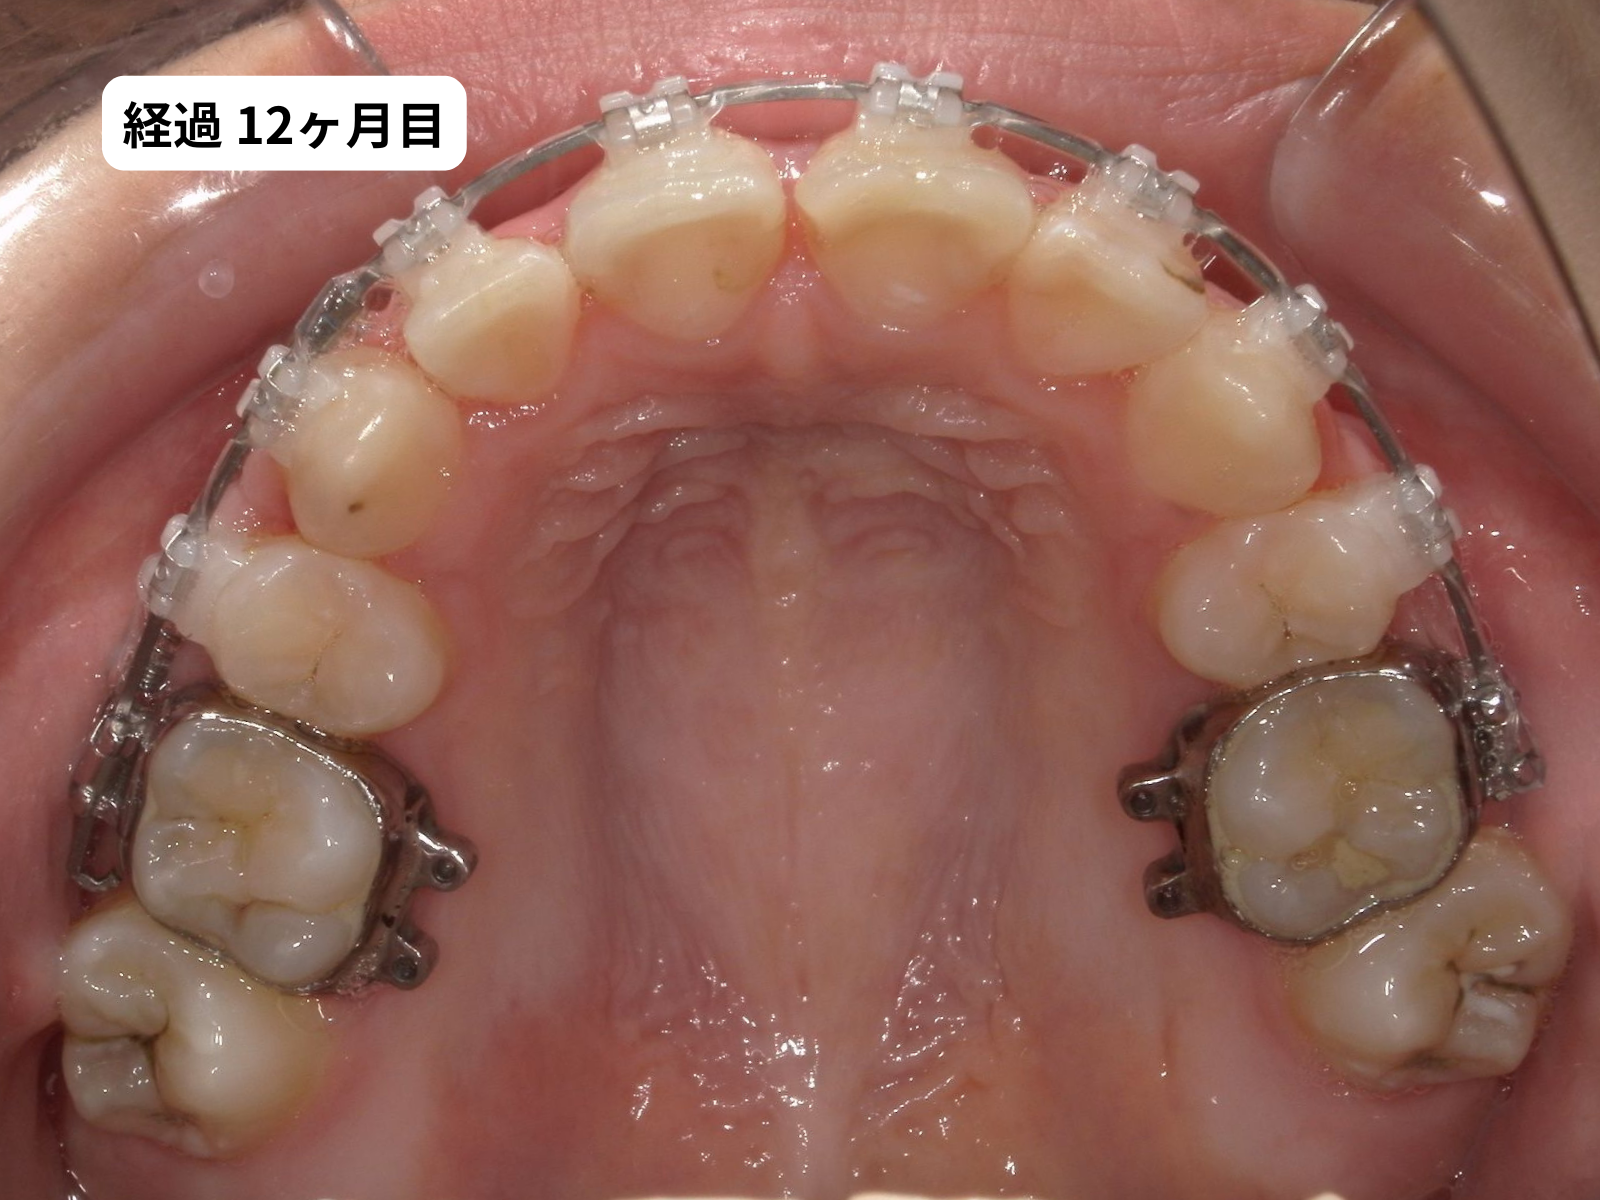

装置装着から1年2ヶ月、毎月の経過

装置をつけた後、上の歯の噛み合わせ面の写真を毎月記録しました。下のスライダーで、月ごとに歯がどう動いていったかをご覧いただけます。

毎月の写真で歯がスムーズに動いているのがわかります。これは 軽い力(約50g)でゆっくり動かす、毎回の来院で移動距離を確認する、この2つを積み重ねた結果です。